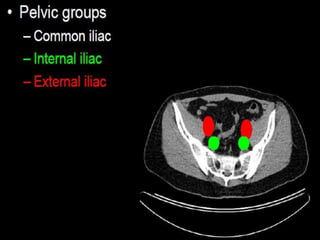

CT cross sectional anatomy.